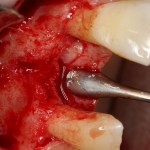

Например, в следующей ситуации:

Оставить так, как есть — это значит, сильно рисковать имплантом и объемом альвеолярного гребня — фактически, большая часть импланта пятого зуба «висит в воздухе». Поэтому получившуюся костную полость мы заполняем аутокостной стружкой в смеси с Bioss и закрываем коллагеновой мембраной BioGide: